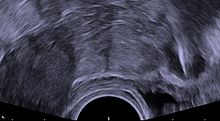

Transvaginal ultrasonography showing a perforated copper IUD as a hyperechoic (rendered as bright) line at right, 30 mm (1.2 in) away from the uterus at left. The IUD is surrounded by a hypoechoic (dark) foreign-body granuloma.